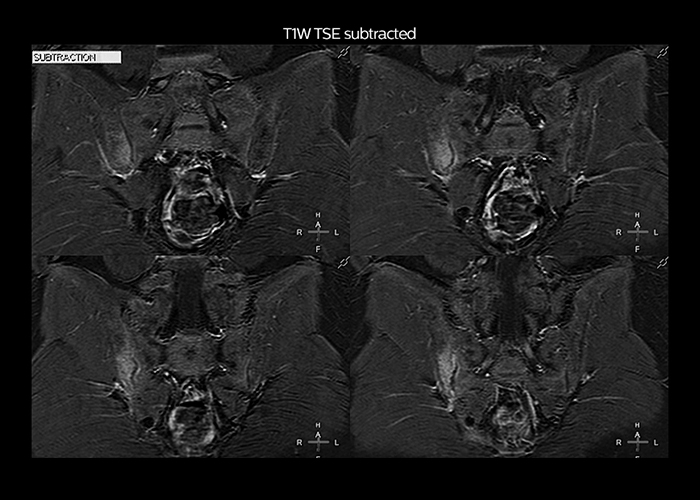

“To avoid coil changes we plan examinations of similar anatomies back to back, such as head and spine. Multiva helps us here a lot because coils don’t need to be changed frequently. Moreover, thanks to parallel imaging technology and 16-channel HeadSpineTorso and 8-channel MSK coils we are able to achieve excellent image quality. In this way Multiva helped us to increase both image quality and productivity.”

“Most important, Multiva satisfies our clinical imaging needs very well,” says Mr. Tuna. “Many features of Multiva have become similar to the Ingenia system. Even in more complex imaging such as abdominal and cardiac, the image quality and performance of Multiva is better than we expected. General surgeons and physicians from our hospital’s internal medicine department prefer to refer to us because of this.”